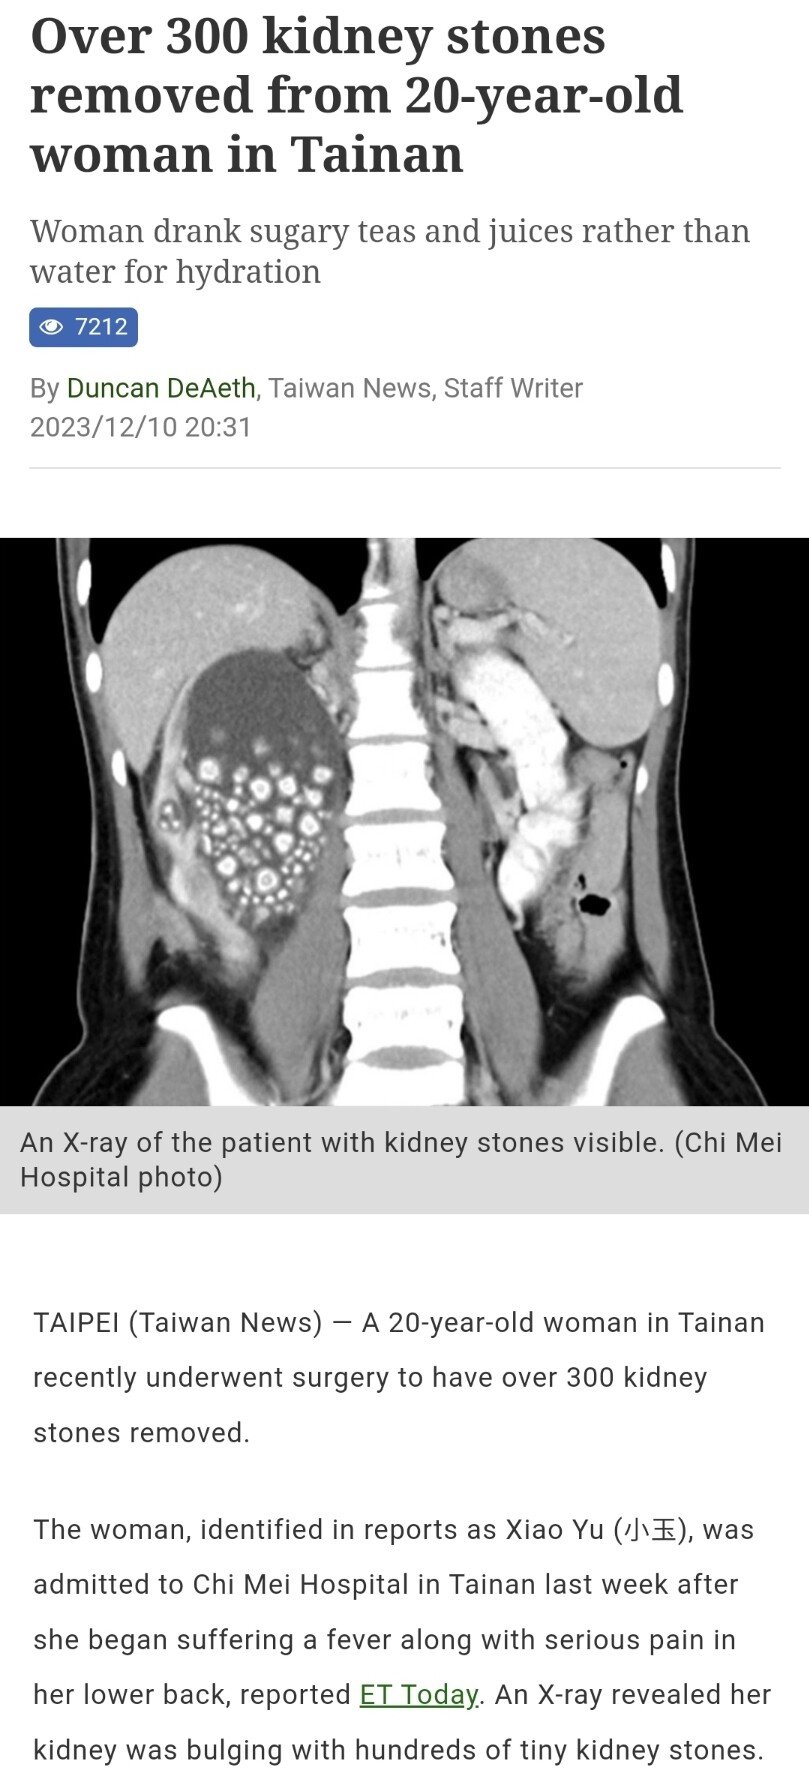

물 마시기를 거부한 대만인 신장결석 300개 제거(혐)